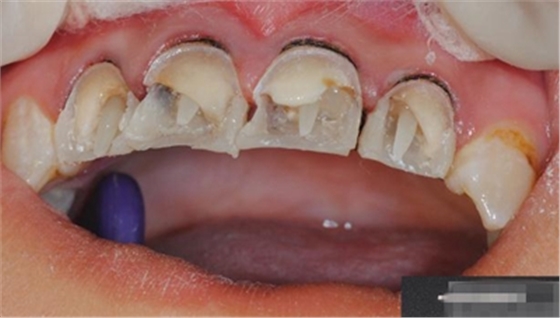

制作 背板

修復(fù)鄰壁

【分層堆塑】

A4本質(zhì)堆塑

Dr.Vanini建議如果牙醫(yī)選色有疑惑的話,最好應(yīng)用顏色深一些的牙本質(zhì)樹脂。

A3本質(zhì)堆塑

發(fā)育葉制作

白堊斑

切端琥珀色制作

A3頸部堆塑

涂布防氧化劑

充填初步完成